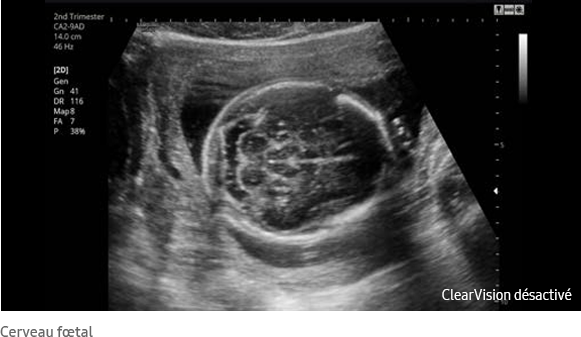

Le filtre de réduction de bruit ClearVision améliore les contours d'une structure anatomique et augmente le rapport signal sur bruit. Il permet de délivrer des images 2D plus nettes et augmente la différenciation tissulaire.